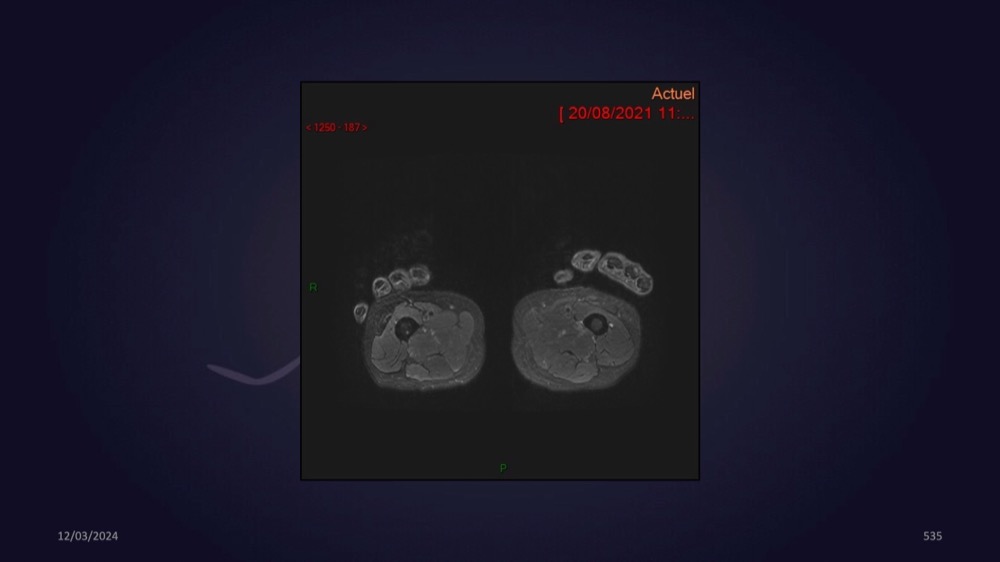

Mezhgani / Dimitri Boulos / Carlier 23/03/2022